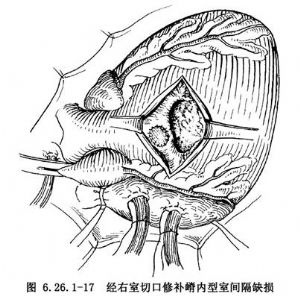

③漏斗部或嵴內缺損修補法:這類缺損全部爲肌肉緣,一般都需應用補片進行修補。缺損緣距傳導組織和肺動脈瓣口均有一定距離,可以應用單純連續縫合法進行縫合,或加用數個帶小墊片的間斷褥式縫線加強縫合(圖6.26.1-17)。